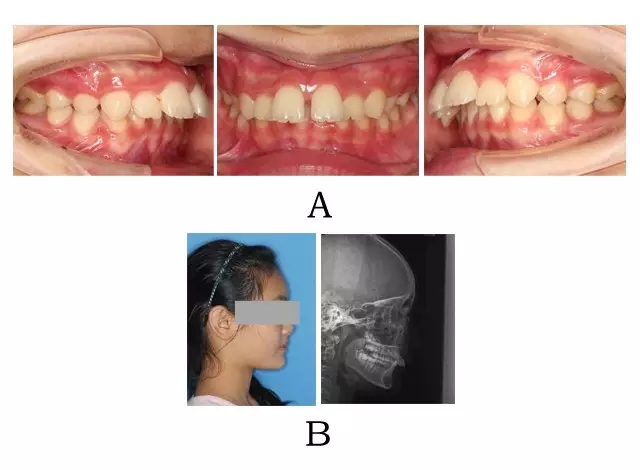

面型前突,唇態(tài)較正常,而下部高度不足、頦唇溝較深,下頜平面較平坦。口內(nèi)表現(xiàn)上頜正?;虬檩p度齒槽性前突,上前牙輕度唇傾。下頜后退,嚴(yán)重的深覆合深覆蓋,磨牙關(guān)系常為遠(yuǎn)中關(guān)系,尖-尖咬合(圖 3-1)。

圖 3-1:頜位性突面畸形臨床表現(xiàn)及頭顱側(cè)位影像特征。

(A)齒槽與牙列特點(diǎn) (B)側(cè)貌與影像對(duì)比

Figure 3-1. Clinical manifestation and cephalometric image for mandibular positional prognathism. (A) Alveolar and dentition specifics. (B) Facial profile and radiographic image.